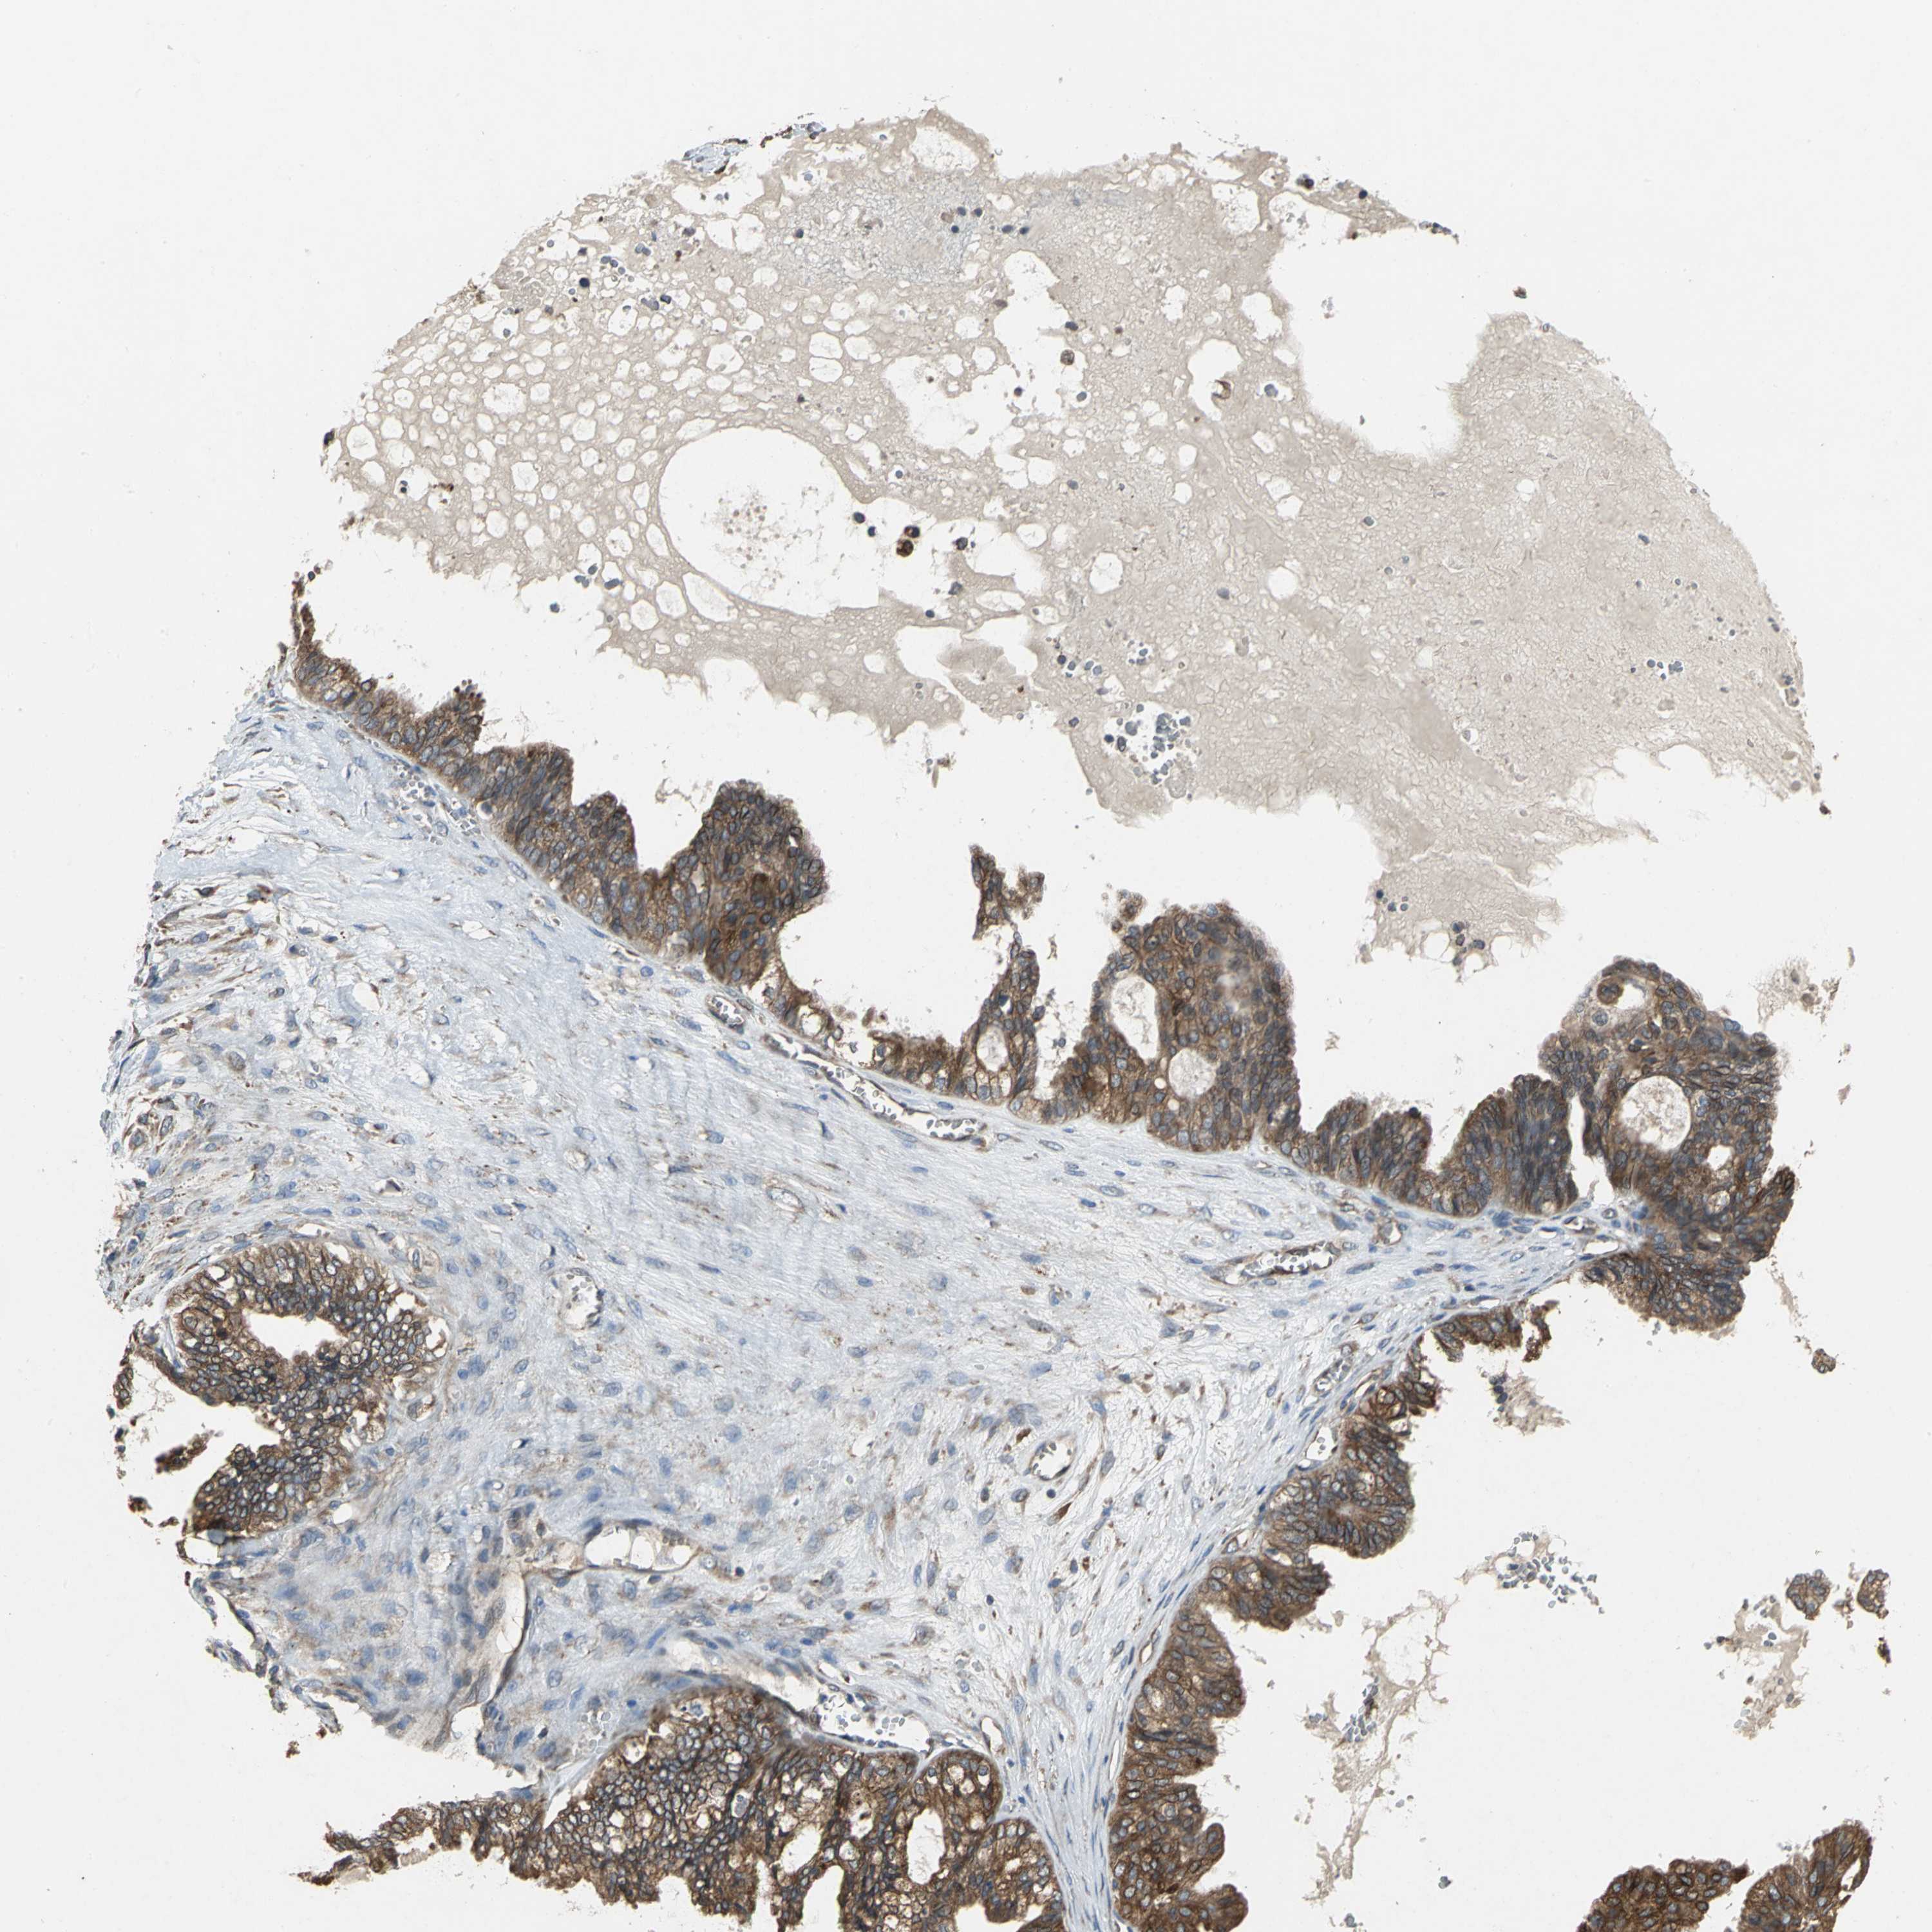

OVARIAN CANCER - Protein expressioni

A mouse-over function shows sample information and annotation data. Click on an image to view it in a full screen mode. Samples can be filtered based on level of antibody staining by selecting one or several of the following categories: high, medium, low and not detected. The assay and annotation is described here.

Note that samples used for immunohistochemistry by the Human Protein Atlas do not correspond to samples in the TCGA dataset.

Antibody stainingi

Antibody staining in the annotated cell types in the current human tissue is reported as not detected, low, medium, or high, based on conventional immunohistochemistry profiling in selected tissues. This score is based on the combination of the staining intensity and fraction of stained cells.

Each image is clickable and will lead to virtual microscopy that enables deeper exploration of all samples and also displays staining intensity scores, fraction scores and subcellular localization as well as patient and tissue information for each sample.

Antibody HPA005480

Antibody HPA024300

Antibody CAB037030

Cystadenocarcinoma, serous, NOS

Carcinoma, endometroid

Carcinoma, NOS

Cystadenocarcinoma, mucinous, NOS